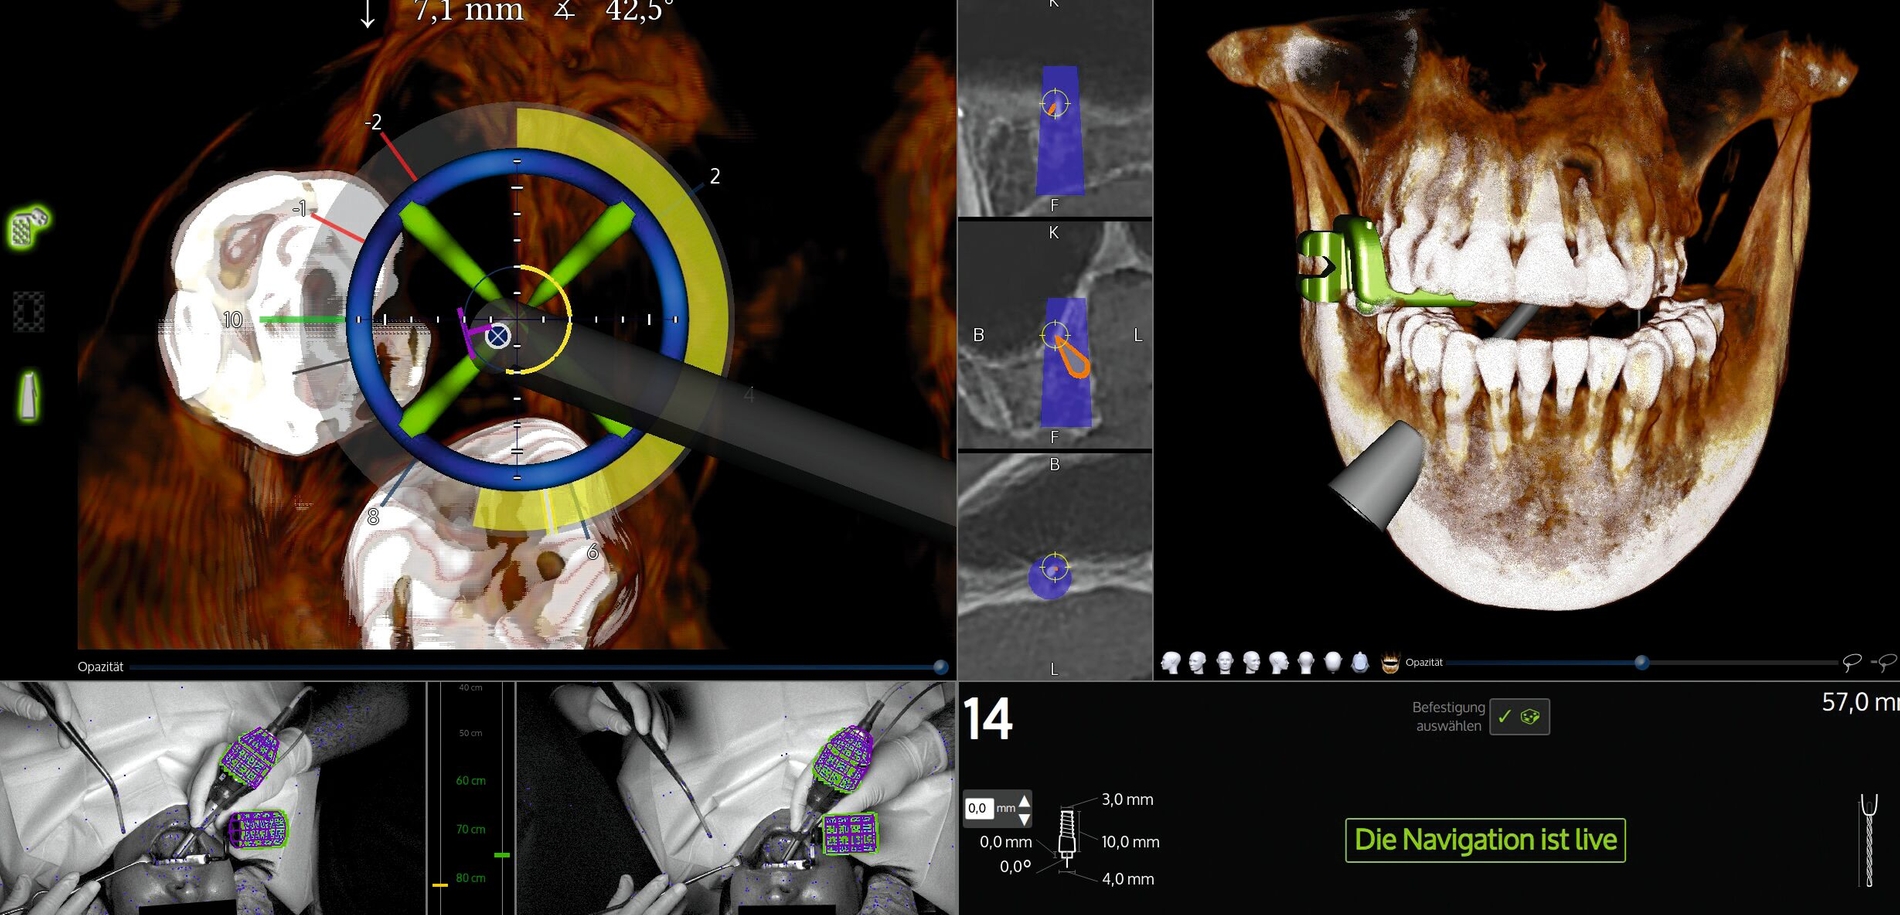

Zur Minimierung des operativen Traumas wurde entschieden, ein dynamisches Navigationssystem (X-Guide®, X-Nav Technologies®, Vertrieb: Nobel Biocare®) einzusetzen. Das System war ursprünglich für die navigierte Implantologie konzipiert worden; die Anwendung zur Fremdkörperentfernung stellt somit einen sogenannten Off-Label-Use dar – worüber die Patientin explizit informiert wurde.

Die dreidimensionale präoperative Planung zeigte, dass das Wurzelkanalinstrument in der palatinalen Wand der linken Kieferhöhle eingebettet war (Abbildung 2a). Um intraoperativ die Mess- und Distanzfunktionen des Navigationssystems optimal nutzen zu können, wurde ein „Simulationsimplantat“ virtuell so geplant, dass der Fremdkörper zentral beziehungsweise apikal im Verlauf des geplanten Implantatkörpers lag (Abbildung 2b).

Der Zugangsweg wurde palatinal gewählt. Nach systemgerechter Kalibrierung erfolgte zunächst eine navigationsgestützte Orientierung, da sich der klinische Situs intraoral komplett reizlos und ohne sichtbare Lagehinweise präsentierte (Abbildung 3). Eine Markierung mit dem Rosenbohrer auf der Schleimhaut diente der exakten Referenz für die Lappenschnittführung (Abbildung 4). Präoperativ wurde zudem eine Verbandsplatte für den Gaumen angefertigt, um die postoperative Stabilisierung zu erleichtern.

Die Schnittführung erfolgte krestal mit einer palatinalen Entlastung (Abbildung 5). Anschließend wurde der knöcherne Zugang zur Kieferhöhle unter kontinuierlicher Navigation gezielt osteotomiert (Abbildung 6). Das Navigationssystem ermöglichte dabei eine präzise Lokalisation des Fremdkörpers und erhöhte die Sicherheit in Bezug auf die angrenzenden Strukturen. Nach vorsichtiger, schrittweiser Osteotomie unter Navigationskontrolle (Abbildung 7) konnte das frakturierte Wurzelkanalinstrument schließlich sicher dargestellt und entfernt werden (Abbildung 8). Zur Auffüllung des entstandenen Defekts wurde ein mit PRF (Mectron®-Verfahren) getränktes Knochenersatzmaterial (Bio-Oss Collagen®, Geistlich®) eingebracht (Abbildung 9). Der Wundverschluss erfolgte spannungsfrei mittels Seidennaht 3-0 (Abbildung 10).